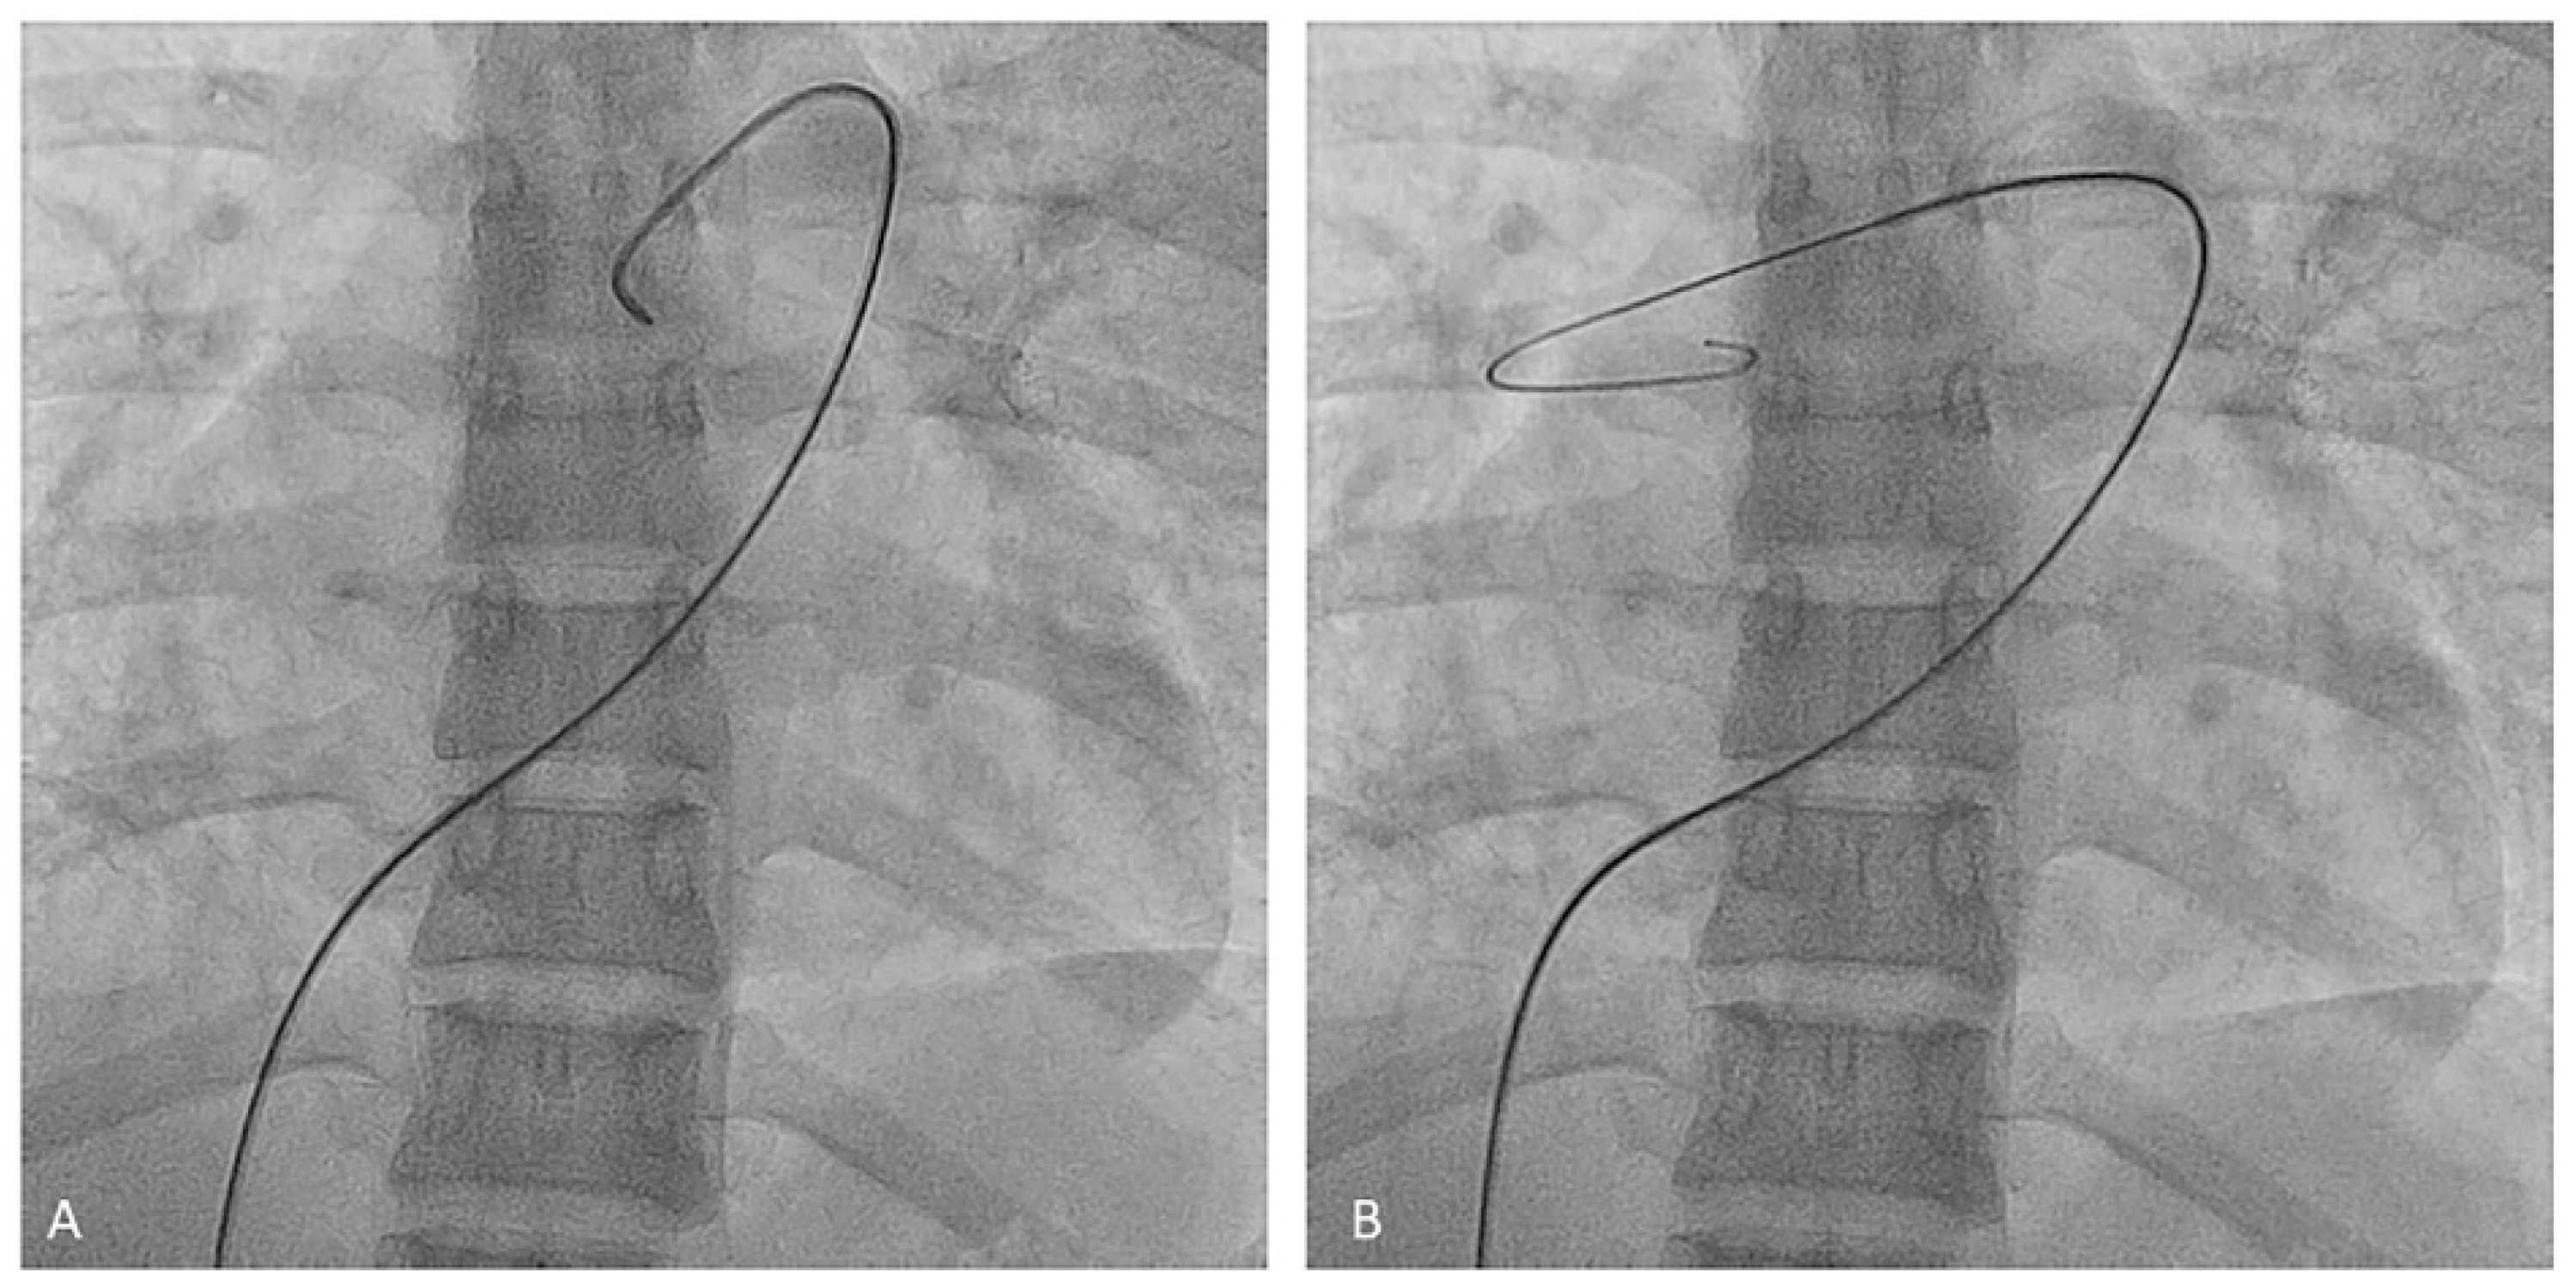

- Left upper lobe. The apico-posterior trunk (A1/2) is easily cannulated in the AP view. We should rotate the MP-A2 catheter counterclockwise in the proximal segment of the LPA to make the tip face upwards (Figure 23). The apical and posterior segmental arteries (A1 and A2) are well visualized by filming in the AP and lateral views. The anterior segmental artery (A3) is engaged more easily with the Judkins left catheter (JL) 3.5 or 4. Position the JL below the aortic arc in the AP view with the distal tip facing the left lateral chest wall. Rotate the catheter counterclockwise and withdraw it slightly. The distal tip of the catheter will climb 2–3 cm, engaging the anterior segmental branch (A3) (Figure 24). Film this branch in the cranial RAO and lateral views.

- Lingula. The lingula artery is easily cannulated in the AP view with the JL 3.5/4 catheter (depending on the PA dilatation). The maneuver and position in the AP view is the same as described for the anterior segmental artery of the left upper lobe (A3), though somewhat lower (Figure 25). Amplatz left 1 or 2 is also a good choice for catheterization of the lingula branches. In addition, this catheter gives extra support when performing BPA of these branches. The two lingula segmental arteries are well displayed in the lateral and in the cranial RAO/cranial AP views.